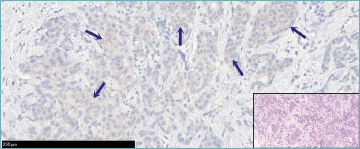

Figure 4. Case 6 from the online collection, showing a distinct quota of neoplastic cells displaying weak and incomplete membranous staining (HER2 1+). Such a sample achieved the highest concordance rate between the participants and the gold standard, with more than 90% of the attendees agreeing with the GIPAM board referral. A corresponding hematoxylin and eosin microphotograph is provided in the inset.

Figure 5. Representative HER2 immunohistochemical pictures of the most controversial cases. A HER2 0+ tumor (online cohort, case 2) arranged in a micropapillary architecture revealing scattered cells with partial membranous staining (blue arrows) (A). HER2 1+ positivity in another case (on-site cohort, case 3), showing a faint but still appreciable expression (blue arrows) in a noteworthy proportion of the cells (11-50%) (B). Weak membranous labeling (blue arrows) in a limited percentage of invasive carcinoma cells (on-site cohort, case 7). Positive elements in adjacent carcinoma in situ foci (red arrows) caused some attendees to score it as HER2 1+ (C). A solid growing tumor enriched with tumor-infiltrating lymphocytes (on-site cohort, case 8) displaying barely noticeable partial membranous HER2 immunostaining (blue arrows) but enough to label the case as HER2 0+ (D). Corresponding hematoxylin and eosin microphotographs for each case are provided in the insets.